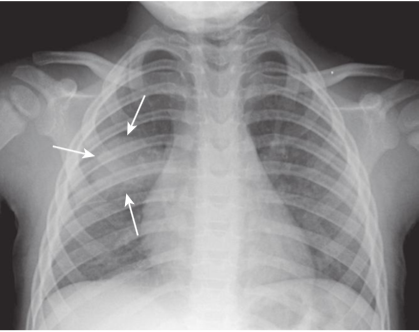

Round pneumonia.

There is a soft tissue density in the right midlung field that has a rounded appearance (white arrows). This is a 10-month-old child who had a cough and fever. This is a characteristic appearance of a round pneumonia, most common in children, and frequently due to either Haemophilus,streptococcal, or pneumococcal infection.